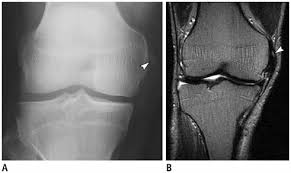

Pellegrini stieda syndrome is a medical problem which is characterized by pain, swelling and inflammation in the knee. It is a common incidental finding on knee radiographs. Pain and restriction of movements. The cause of the knee effusion is unknown. There is a moderately large knee effusion. The diagnosis pellegrini stieda disease was made. Is the presence of a radiological finding of calcification on the medial side of the knee as a consequence. It is likely that this patient has been an active sportsman in the past.

Pain and restriction of movements. The cause of the knee effusion is unknown. It is likely that this patient has been an active sportsman in the past. #foamed #foamrad #radiology #rad #elearnrad #voxelz #varunbabu #drbabu. Pellegrini stieda syndrome is a medical problem which is characterized by pain, swelling and inflammation in the knee. Most of the cases of pellegrini stieda lesions are not symptomatic, and pellegrini stieda syndrome is said to exist when the lesion becomes symptomatic i.e. Ayurvedic treatment is the natural way to treat pellegrini stieda syndrome. Is the presence of a radiological finding of calcification on the medial side of the knee as a consequence. The diagnosis pellegrini stieda disease was made. It is a common incidental finding on knee radiographs. With the ayurvedic treatment, it is possible to avoid surgery. This occurs due to the deposition of calcium on the inner side of the knee. Learn about this soft tissue calcification around the knee joint.

Pellegrini stieda syndrome is a medical problem which is characterized by pain, swelling and inflammation in the knee. The diagnosis pellegrini stieda disease was made. Learn about this soft tissue calcification around the knee joint. The cause of the knee effusion is unknown. There is a moderately large knee effusion. Pain and restriction of movements. Is the presence of a radiological finding of calcification on the medial side of the knee as a consequence. It is a common incidental finding on knee radiographs. Most of the cases of pellegrini stieda lesions are not symptomatic, and pellegrini stieda syndrome is said to exist when the lesion becomes symptomatic i.e. #foamed #foamrad #radiology #rad #elearnrad #voxelz #varunbabu #drbabu. It is likely that this patient has been an active sportsman in the past. There is evidence of osteoarthritis. This occurs due to the deposition of calcium on the inner side of the knee.